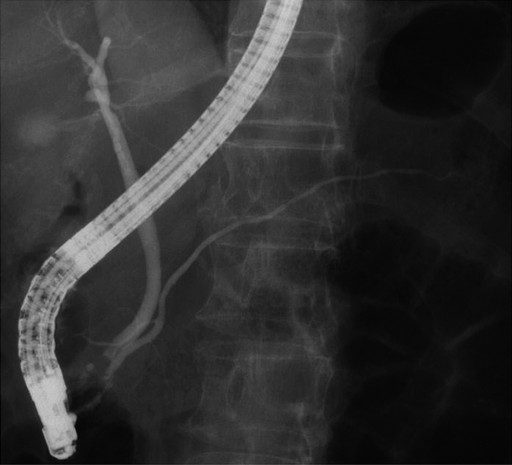

An esophagogastroduodenoscopy showed normal findings. Diseases such as reflux esophagitis and gastric ulcer were not observed. Ultrasonography (Figure 1) revealed a markedly heterogeneous pancreatic parenchyma demarcated from the neighboring tissues. The main pancreatic duct was not narrowed or dilated, and no tumor was detected. A CT image is shown in Figure 2. Plain CT (Figure 2a) revealed that the density of the pancreatic parenchyma had uniformly decreased to the same level as that of the surrounding fatty tissue. Contrast-enhanced CT (Figure 2b) revealed that the entire pancreatic parenchyma was absent and only a contrast-enhancing net-like shadow was visible. The magnetic resonance imaging (MRI) image is shown in Figure 3. The T1-weighted image could confirm that the entire pancreas was completely absent on T1-weighted images (fat suppression) (Figure 3). Endoscopic retrograde cholangiopancreatography (ERCP; Figure 4) showed no anomalous arrangement of the pancreaticobiliary ducts or pancreatic duct anomaly. Furthermore, obstruction, narrowing or dilatation of the main pancreatic duct was not observed. The branches of the pancreatic ducts appeared normal on the ERCP image. No abnormalities were observed in the bile duct.

Figure 4. Endoscopic retrograde cholangiopancreatography: There is no anomalous arrangement of the pancreaticobiliary ducts or any anomaly of the pancreatic ducts. Obstruction, narrowing or dilatation of the main pancreatic duct is not observed. The pancreatic duct branches appear normal. No abnormalities of the bile duct are observed. |

When making a differential diagnosis, the following disorders need to be considered in relation to lipomatous pseudohypertrophy of the pancreas: obesity, diabetes and age-related pancreatic fat infiltration. Olsen [7] investigated the autoptic findings of 349 cases and observed that different levels of pancreatic fat infiltration were present in all cases, indicating that pancreatic infiltration is associated with aging and obesity. Many patients with diabetes often show similar fat infiltration. However, the imaging findings of these patients revealed a remnant pancreatic parenchyma with uneven fat infiltration, which is different from the uniform fatty replacement obtained in the present case. Meanwhile, fatty replacement associated with the obstruction of the main pancreatic duct induced by pancreatic cancer or chronic pancreatitis should be distinguished from lipomatous pseudohypertrophy of the pancreas. In the present case, ERCP did not reveal any narrowing or obstruction of the main pancreatic duct, and CT, MRI and endoscopic ultrasonography did not indicate any tumor in the pancreas. Further, liposarcoma should also be distinguished from lipomatous pseudohypertrophy of the pancreas; factors such as the presence/absence of jaundice, morphological uniformity/non-uniformity, and imaging of the pancreatic ducts are useful in identifying lipomatous pseudohypertrophy of the pancreas.